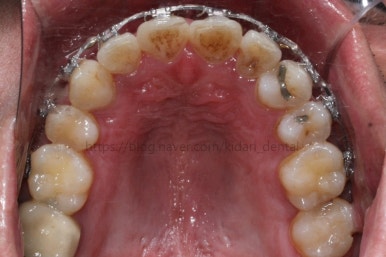

부산치아교정 키다리아저씨치과에 처음 내원 당시의 입안 모습입니다.

여러 가지 문제점이 있는데 하나씩 살펴볼게요.

치열이 많이 삐뚤하네요.

많이 삐뚠 상태에서 장기간 사용하다 보면 안좋은 방향으로 치아가 힘을 받게 되고 마모나 치아 목부분 패임이 심해집니다.

양치가 힘들어요. 양치가 힘들다 보니 세게 닦게 되고 치아 손상은 더 심해져요. 25세의 나이였는데 나이에 비해서 치아나이가 굉장히 많은거죠.

화살표 부분에 원래 송곳니가 있어야 되는데 보이질 않네요. 결손치아일 수도 있고 매복치아일 수도 있겠어요.

왼쪽 위 어금니도 한 개가 없어서 빈공간이 약간 남아있어요.

왼쪽 아래 작은 어금니는 아래쪽으로 많이 꺼져있네요.